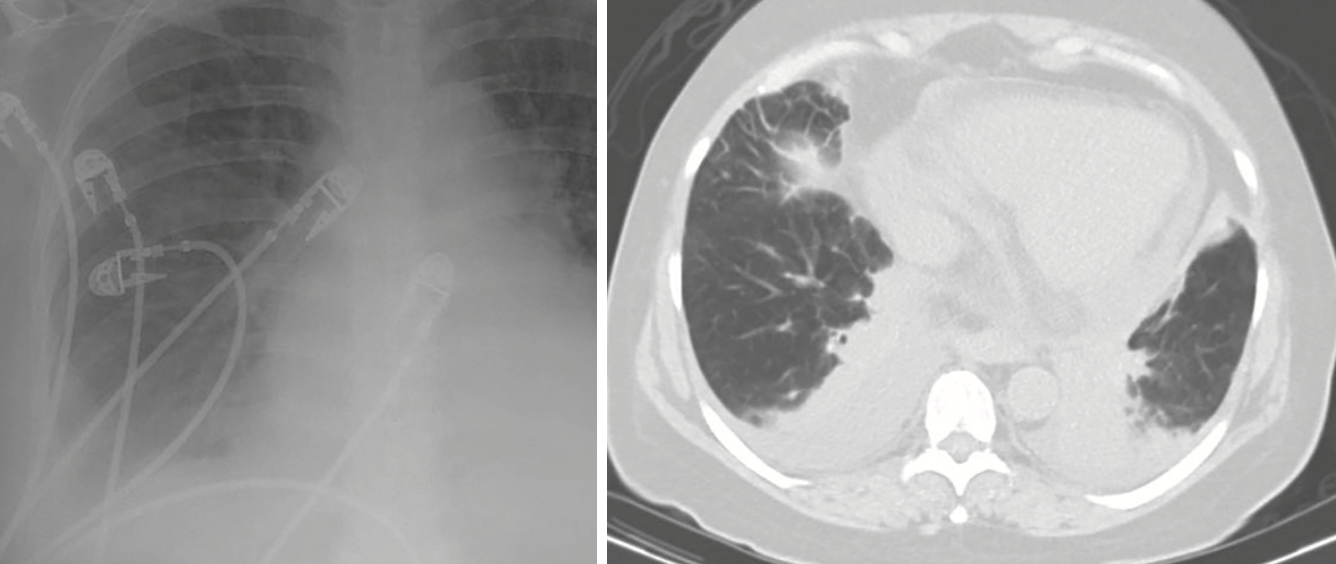

Carlito Arenas, Jr., MD; Vincent Bryan Salvador, MD; Sabaa Joad, MD; Arunakumari Penumadu, MD; Valeriy Vilensky, MD

A 25-year-old African American, G2P2, without prior known comorbidities presented to the emergency department with 2 episodes of seizures, 8 days after an uncomplicated full-term normal spontaneous vaginal...